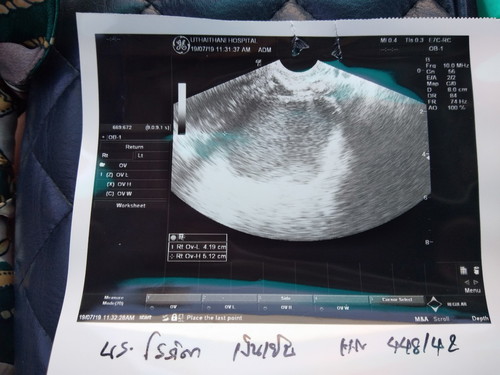

คือพึ่งตั้งครรภ์ได้9wมีอาการปวดท้องน้อยแบบหน่วงๆและปวดบั้นเอว ลงสะโพกต้นขา พอไปหาหมอตรวจเจอก้อนซีสตรงปีกมดลูกขวา ขนาดก้อน 4 ซม. กว่า และหมอนัดอีกทีวันที่16 สค. คือตอนนี้เป็นกังวลว่า จะมีผลกระทบอะไรกับลูกในท้องไหมค่ะ รบกวน แม่ๆท่านไหนมีประสบการณ์ช่วยแนะนำหน่อยค่ะ ตอนนี้เครียดและกังวลมาก